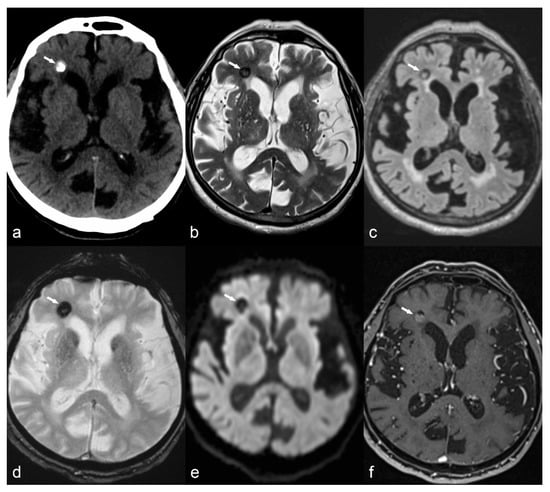

Figure 3.

Patient with tuberosis sclerosis complex: the interictal Single-photon emission computed tomography (SPECT) and fluorodeoxyglucose-positron emission tomography (FDG-PET) (fused with MRI FLAIR images) show multiple hypometabolic foci, corresponding to the multiple tubers. Ictal SPECT shows ictal hyperperfusion of the superior right frontal tuber.

Ictal SPECT with perfusion tracers is the only technique able to show the perfusion changes occurring during the epileptic event: two acquisitions are usually performed, in the ictal and interictal condition (as exemplified in Figure 3) and digital subtraction techniques are used to complement visual interpretation to identify the subtlest changes associated with the seizure.

The most commonly used imaging strategy is 18F-fluorodeoxyglucose positron emission tomography (FDG-PET) in the interictal state, allowing detection of focal areas of relative hypometabolism, that are presumed to reflect focal functional disturbances of cerebral activity associated with the epileptogenic tissue, as exemplified in Figure 3 [62,63]. The interpretation of FDG-PET images with the support of automated semiquantitative approaches and with a systematic fusion of PET and MRI has a relevant diagnostic added value, namely for neocortical epilepsy [64]. For this purpose, technological developments, namely the availability of new hybrid tomographs allowing PET and MRI imaging in a single session, provide an ideal tool for a comprehensive investigation of epileptic patients [65,66]. Recent studies have also suggested that focal FDG-PET abnormalities carry not only diagnostic but also prognostic information and are a predictive factor for a positive surgical outcome, both in temporal and extratemporal epilepsy [64]. Finally, PET imaging using specific molecular tracers also allows the assessment of various neurotransmission systems, with promising results in clinical research applications [67].